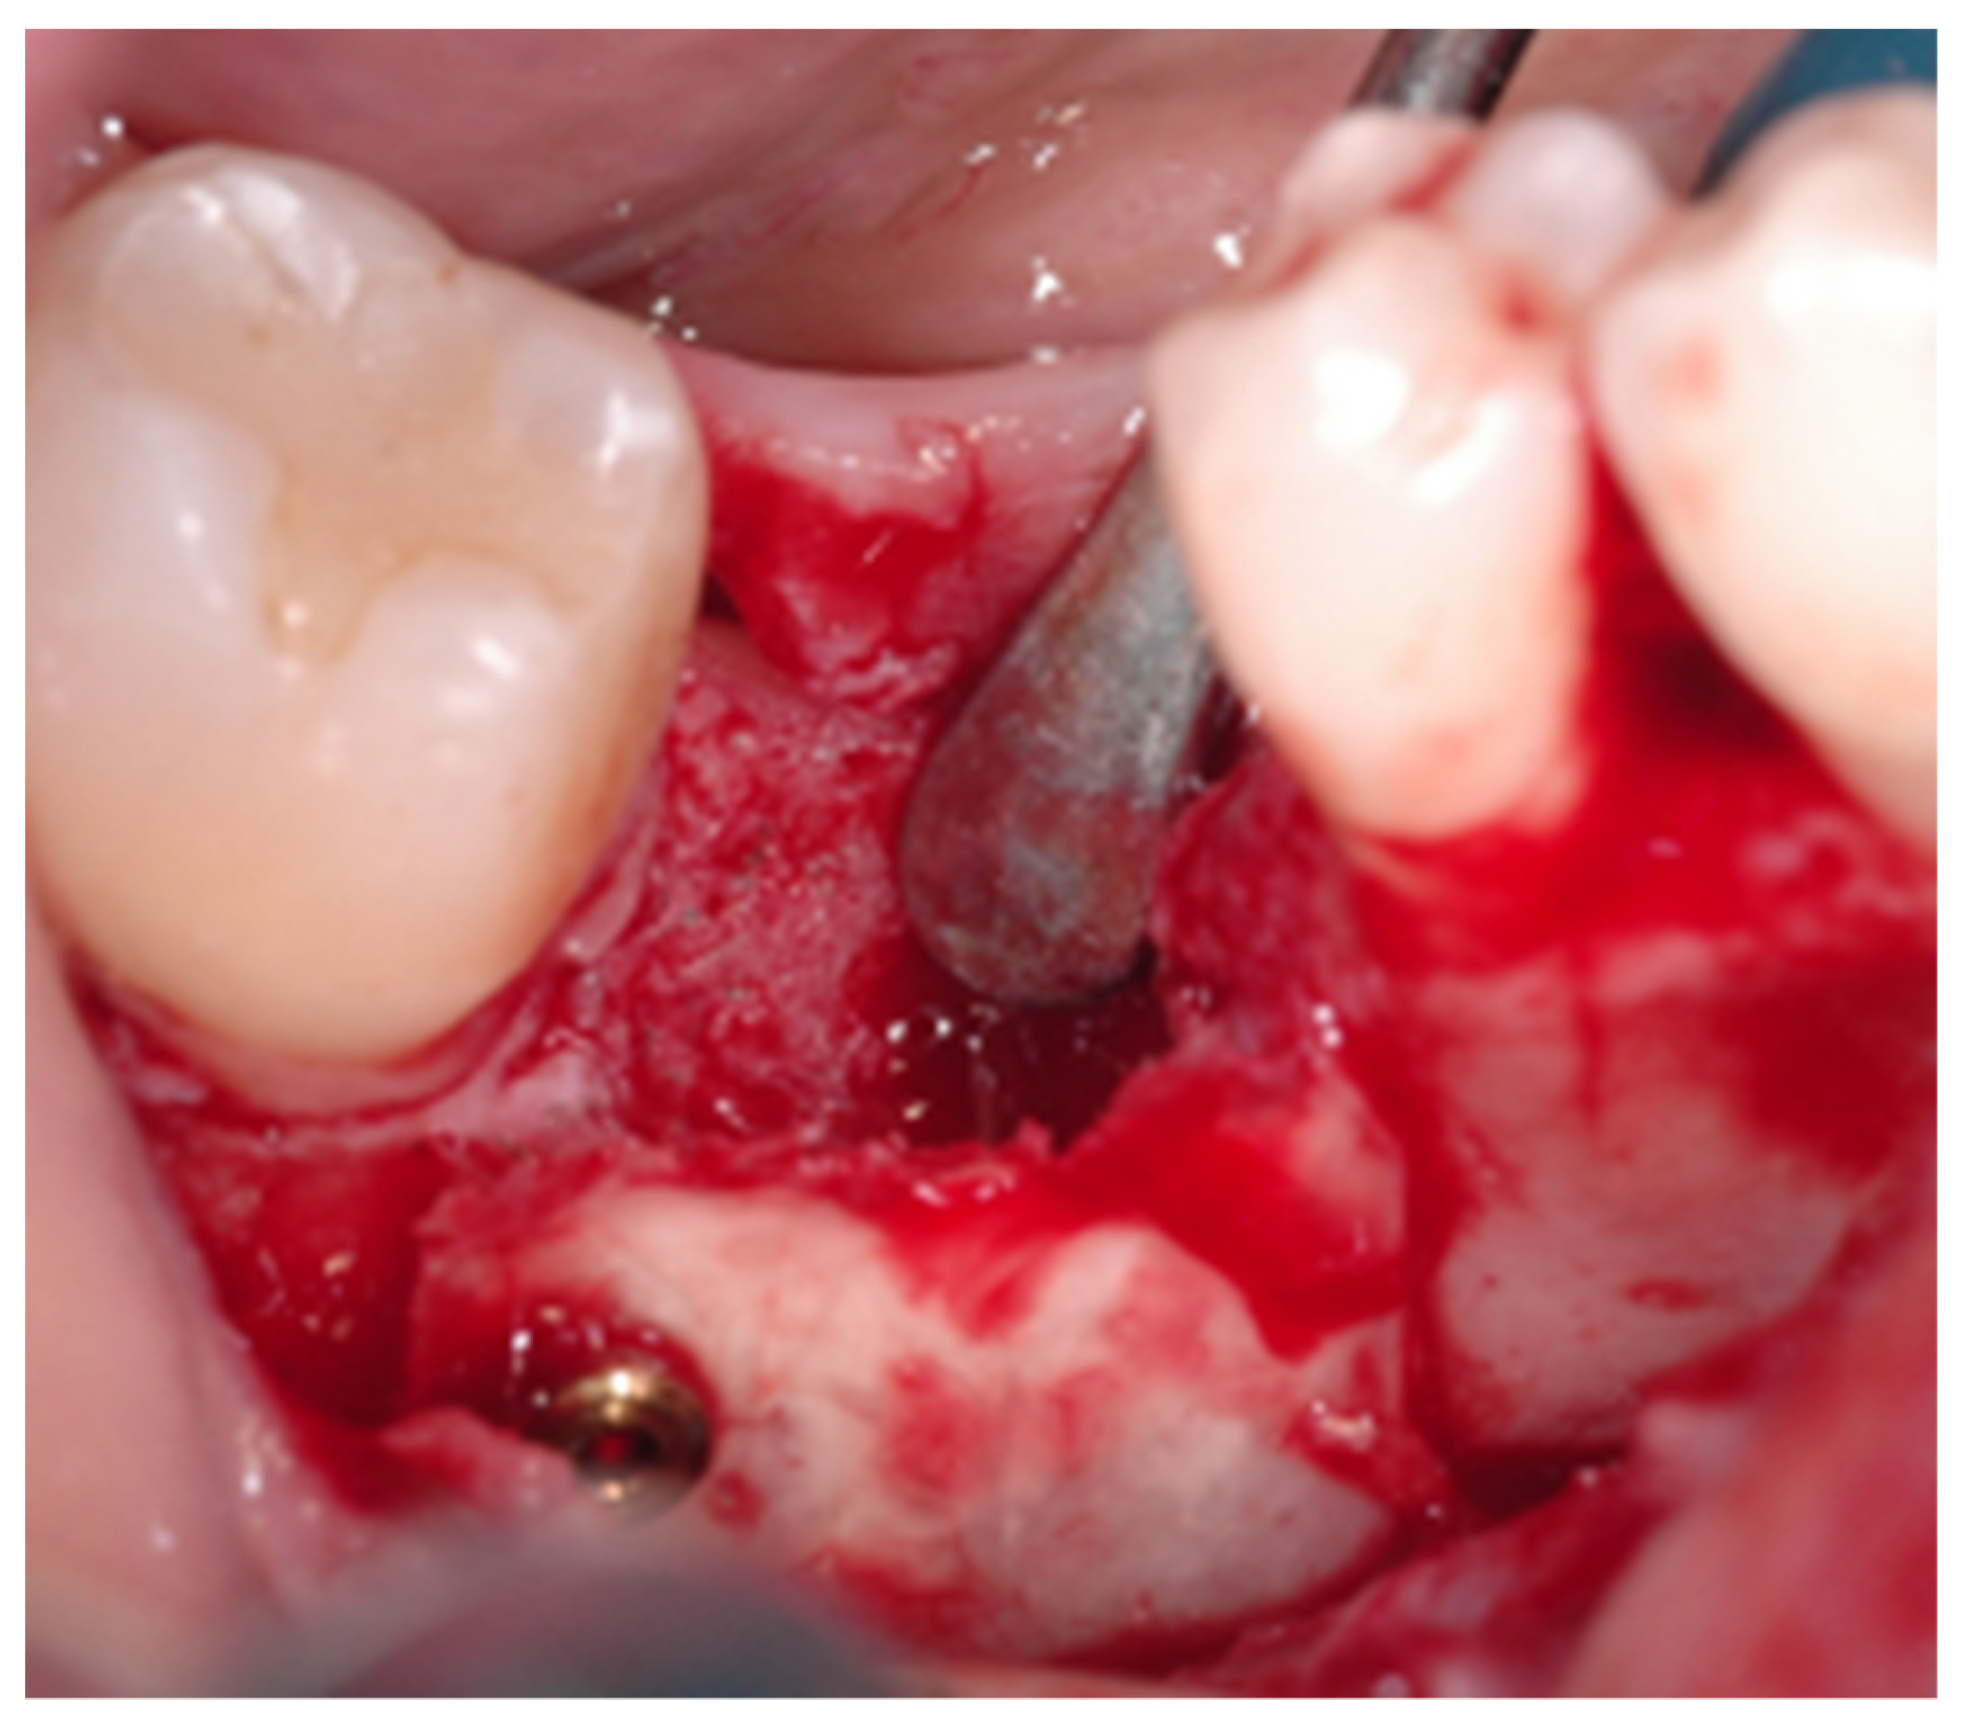

2.2. Surgical Procedure